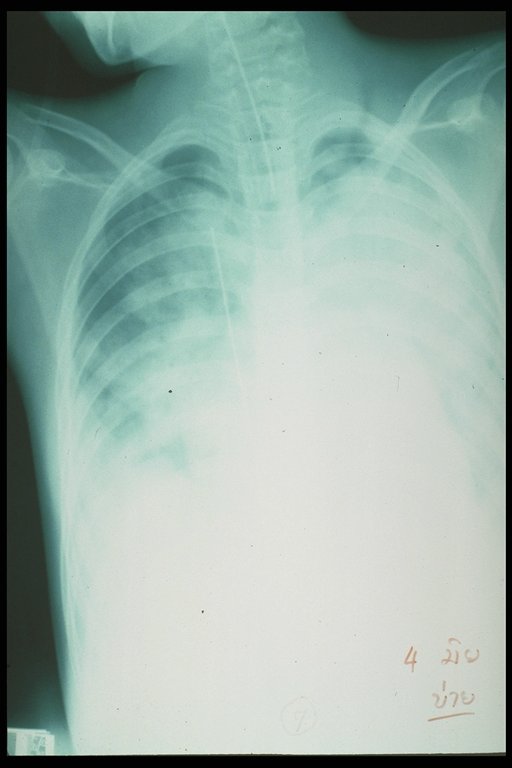

Retained guidewire in the Inferior vena cava after angiography (film chest)